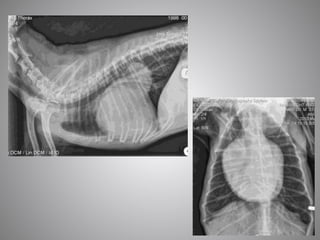

• #27 HCM severe HF Cats are more difficult than dogs The left atrium sits further forward n the lateral view making It harder to tell in there is cardiomegaly on this view In this particular cat however, there is a huge left auricle on the DV view. The lung pattern is also more difficult in cats. In this particular cat it looks almost miliary in appearance which may lead one to think that neoplasia may be the cause of the cats signs However, due to the obviously large left atrium, I would treat this cat with frusemide then confirm this suspicious with echo (once stable). This cat had also thrown a distal aortic thromboembolus hence, the presence of the fentanyl patch for pain relief.

• #28 HCM, early CHF large LA

• #29 HW cat Not CHF